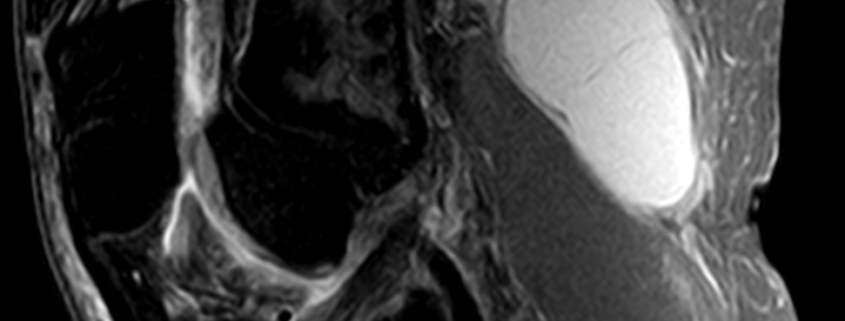

Your doctor may be able to diagnose a popliteal cyst by examining your knee. They may also use imaging tests, such as ultrasound or MRI, for a more detailed view of the joint. In some cases, a cyst may be aspirated – a procedure involving drawing fluid from the cyst with a needle for examination.